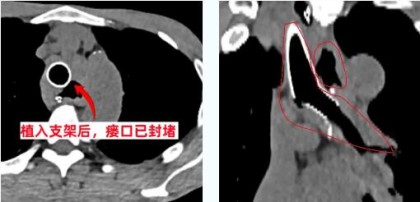

这是一场与死神的搏斗,争分夺秒的营救。麻醉状态下可能导致气道阻塞而缺氧加重,加大了手术和麻醉难度。呼吸介入团队凭借丰富的手术经验,历时30分钟顺利完成手术,支架植入位置精准,膨胀良好、贴壁完全,有效覆盖了患者的气管食管瘘口。

术后蒋先生咳嗽、咳痰、流质饮食呛咳症状明显好转,复查胸部CT原瘘口已被支架完全覆盖、肺部感染明显好转。